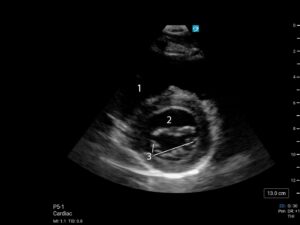

Parasternale asse lungo (PLAX)

Piano di scansione parallelo all’asse lungo del ventricolo sinistro, che interseca l’apice del ventricolo sinistro, il centro della valvola aortica, e il centro della valvola mitrale in senso antero-posteriore

Posizione della sonda

La sonda deve essere posizionata lungo la linea parasternale sinistra con il marker rivolto verso la spalla destra del paziente, e scorrendo tra i vari spazi intercostali (generalmente tra il terzo e il quinto) si trova la finestra che garantisce la migliore visione.

In questa visione è possibile vedere parte del ventricolo destro, la valvola aortica e l’aorta ascendente prossimale, l’atrio sinistro, la valvola mitrale e le pareti anterosettali e inferolaterali del ventricolo sinistro.

- Ventricolo destro

- Ventricolo sinistro

- Valvola aortica / radice dell’aorta ascendente

- Valvola mitrale

- Atrio sinistro

- Aorta Discendente

- Pericardio

Si valutano

- Ventricolo destro: questa finestra non è la migliore per la valutazione delle dimensioni o della funzionalità del ventricolo destro, ma è possibile notare marcate dilatazioni o disfunzioni di parete. Normalmente la porzione di ventricolo destro osservabile da questa finestra ha dimensioni comparabili a quelle della radice aortica.

- Valvola aortica: una stenosi valvolare è improbabile se la valvola si apre completamente e rapidamente.

- Atrio sinistro: se dilatato e notevolmente più grande rispetto al diametro della radice dell’aorta suggerisce una possibile storia di pressioni atriali sinistre elevate come da disfunzione diastolica, malattie valvolari mitraliche o fibrillazione atriale.

- Valvola mitrale: dovrebbe aprirsi rapidamente in diastole e chiudersi completamente in sistole. Se i lembi della valvola mitrale superano l’anulus mitralico durante la sistole possono indicare prolasso o ribaltamento della valvola mitralica con insufficienza valvolare. Se il lembo anteriore della valvola mitrale non si apre rapidamente, avvicinandosi alla parete anterosettale del ventricolo in diastole, si potrebbe pensare a stenosi valvolare. Lembi valvolari rigidi durante l’apertura possono indicare malattia reumatica valvolare. Un’altra anomalia osservabile in questa visione è un eccessivo movimento anteriore del lembo anteriore della mitrale durante la sistole, che potrebbe indicare un problema di ostruzione dinamica del tratto di efflusso del ventricolo sinistro (LVOT, ovvero il tratto di ventricolo che precede immediatamente la valvola aortica), reperto comune nei pazienti con cardiomiopatia ipertrofica o in pazienti con ventricolo sinistro piccolo e spesso o tessuto valvolare in eccesso; in questi casi, come per ogni difetto valvolare di entità rilevante, si raccomanda una valutazione specialistica.

- Si può avere una valutazione globale del ventricolo sinistro in questa visione nonostante siano osservabili direttamente solo la porzione anterosettale e inferolaterale della parete ventricolare. Inizialmente si può valutare la morfologia del ventricolo, per esempio se la camera appare dilatata o se il tessuto miocardico è ipertrofico. Dopodiché si può valutare la contrattilità: il miocardio si dovrebbe contrarre (ispessimento della parete e avvicinamento di apice e base del ventricolo) rapidamente in sistole. Altri segni qualitativi di buona funzionalità ventricolare includono l’oscillazione antero-posteriore della radice dell’aorta (anteriormente con il riempimento atriale e posteriormente con lo svuotamento atriale) e buona escursione del lembo mitralico anteriore.

- In questa finestra è talvolta possibile osservare la presenza di versamento pericardico, che è eventualmente osservabile come una zona anecogena compresa tra il cuore e l’aorta discendente toracica.